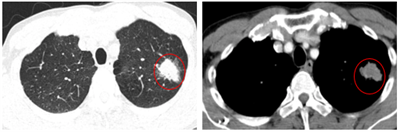

Ca lâm lâm sàng  Bệnh nhân mắc hai ung thư nguyên phát: Ung thư phổi không tế bào nhỏ và Ung thư trực tràng

Ngày đăng: 22/01/2026

Đa ung thư nguyên phát được định nghĩa là sự xuất hiện nhiều khối u ác tính nguyên phát, khác nhau về mô bệnh học, trên cùng một bệnh nhân. Nhờ sự phát triển của các kỹ thuật chẩn đoán hình ảnh và...